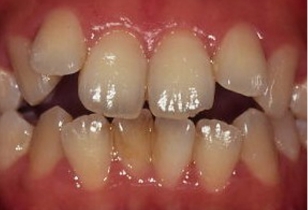

伊藤矯正歯科医院での安定した症例

これに対し伊藤矯正歯科医院では、抜歯を伴う矯正を行ったのちに何も装置を使用しなくて何年か経過しても、かなり安定している症例をみることが多くありました。(「安定調査症例1~4」と当HPの症例集ページ「叢生第3,4症例」をご覧下さい。)そこで治療が終わって数年経過した時点で、資料採得のできた14症例について歯並びの変化を観察しました。